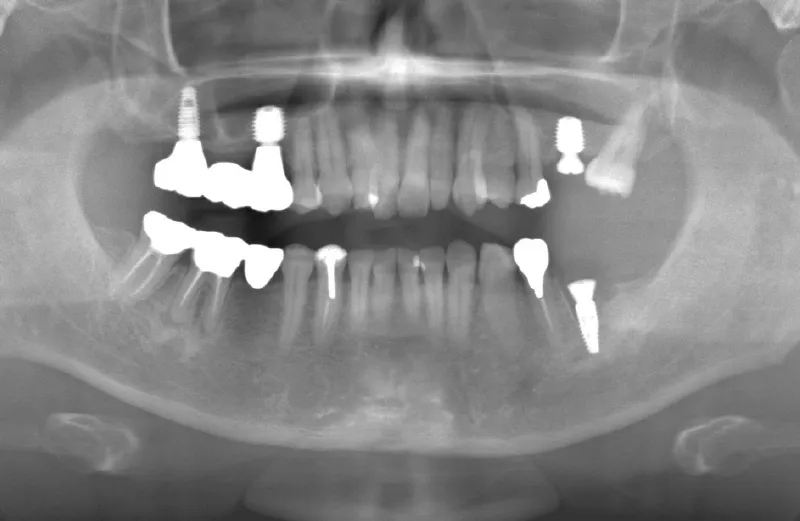

メガジェンオペの症例紹介02

治療前

治療後

| 主訴 | 入れ歯は以前に入れたことがあるが違和感が強く入れられなかった。これ以上歯を失いたくないので右上をインプラントで治療して欲しい。その他の歯もなるべく残して欲しい。 他院では右上は上顎洞までの垂直骨量が2~3mm程度しかないのでサイナスリフトが必須であり、インプラント治療に1年以上かかると言われたのでセカンドオピニオンを希望で来院。 |

|---|---|

| 治療期間 | 2.5ヶ月で仮歯が入り、 4ヶ月で最終補綴物が入って終了。 |

| 治療費 | 約1,500,000円 |

| 治療内容 | エクストラワイドショートインプラントを埋入し、上顎洞を移植材を用いずに挙上しインプラントを埋入した。約2.5ヶ月で仮歯を装着し、様々な機能面に問題がないことを確認し4ヶ月で最終補綴物を装着して終了した。 |

| 治療の リスク |

インプラント埋入オペ時に術者が上顎洞内にインプラントを迷入させる可能性がある。これは術者が技術的に熟練していれば防ぐことが可能。 |